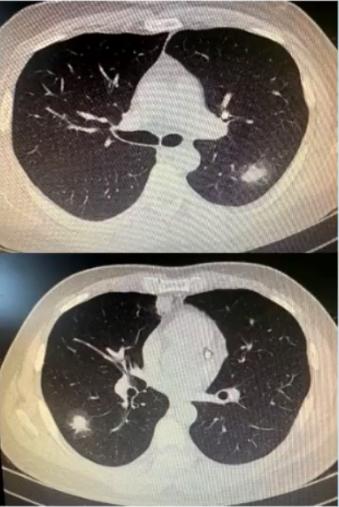

图1 患者的影像学以实变为主